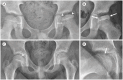

Developmental dysplasia of the hip is a condition characterized by hip joint instability due to acetabular dysplasia in infancy, necessitating precise ultrasound examination. Legg-Calvé-Perthes disease is caused by a temporary disruption in blood flow to the femoral head during childhood, progressing through avascular, fragmentation, re-ossification, and residual stages. Slipped capital femoral epiphysis is a condition where the femoral head shifts medially along the epiphyseal line during adolescence due to stress, such as weight-bearing. Differentiating between transient hip synovitis and septic arthritis may require joint fluid aspiration. Osteomyelitis can be associated with soft tissue edema and osteolysis. When multiple lesions are present, it is essential to distinguish between Langerhans cell histiocytosis and metastatic neuroblastoma. This review will introduce imaging techniques and typical findings for these conditions.